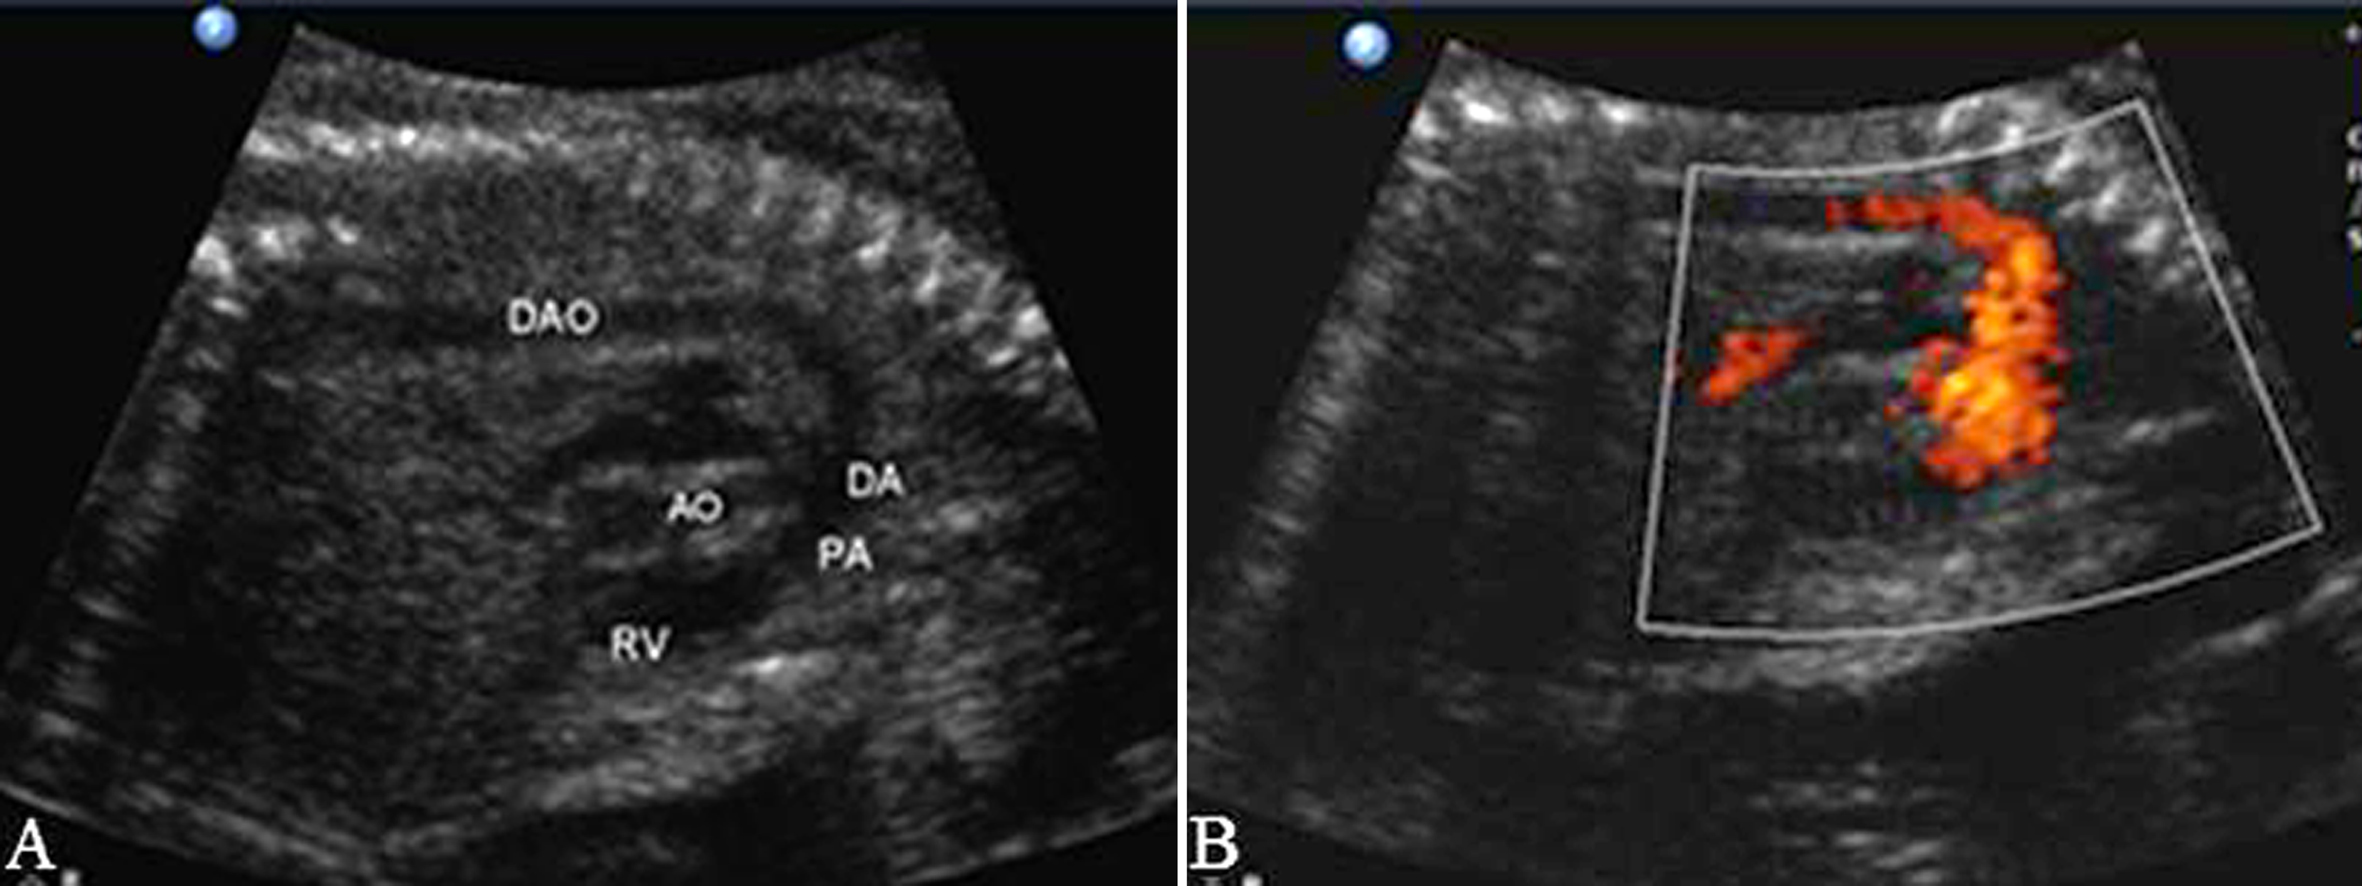

三、动脉导管

主动脉弓长轴和PA之间可以显示动脉导管(DA)及其血流(图5、图6)。正常DV显示为单向、单峰性搏动性频谱,PI>2.0。

图5 动脉导管切面观(脊柱前位)(A)及对应血流(B)

图6 动脉导管切面(脊柱后位)(A)及对应血流(B)

由于胎肺血管没有形成正常的充盈状态,RVO流出的血液绝大多数经DA进入降主动脉,PA的阻力明显大于AO。在AO和PA的起始部,AO的血流速度明显大于PA,速度比为1.3:1,而在PA远端,由于较大的DA两端压差而使其内部的血流速度达到140cm/s。胎儿出生后,随着呼吸的开始和肺的充气,肺循环阻力迅速下降,尤其是在胎儿出生6小时以后,肺充气的面积迅速扩大,肺循环阻力下降尤为明显,但血流速度一直小于AO。

在不同妊娠期动脉导管的血流有一定的变化。收缩期血流峰值速度SV=3.34×孕龄-4.59,与心率没有明显的相关性,与PA瓣口的血流速度比值为1.35;舒张期血流峰值速度DV=0.57×孕龄-0.31,与胎儿心率没有明显的关系,但胎儿心率的增加可以提高舒张末期血流速度;加速时间AT=2.11×孕龄+19.2。